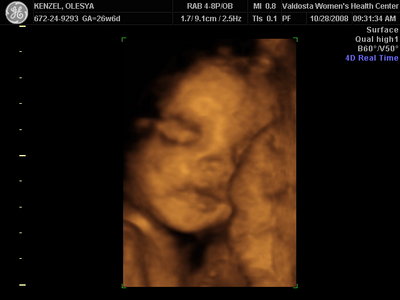

Ксюнь, а мы вообще не поняли. Она на всех фотках разная, да еще размытость такая. Пуповина то на носу болталась, то руками-ногами закрывалась. Главное что четкости нет совсем. Лоб у мужа тоже большой, а носы и губы зачастую на 3Д-4Д выходят разамазанно-пухло-приплюснутыми Поставлю для наглядности фотку моей средней-Джианки с 3Д УЗИ, там видно черты намного лучше и она на себя ту похожа сейчас, хотя родилась мне совсем на фото УЗИ не казалась похожей.

Вложения: |

KENZEL,OLESYA_3.JPG [ 56.84 КБ | Просмотров: 1154 ]

Катюш, какой прикольный бутузик ! Олесь, после фотки средней - точно прям похожи!